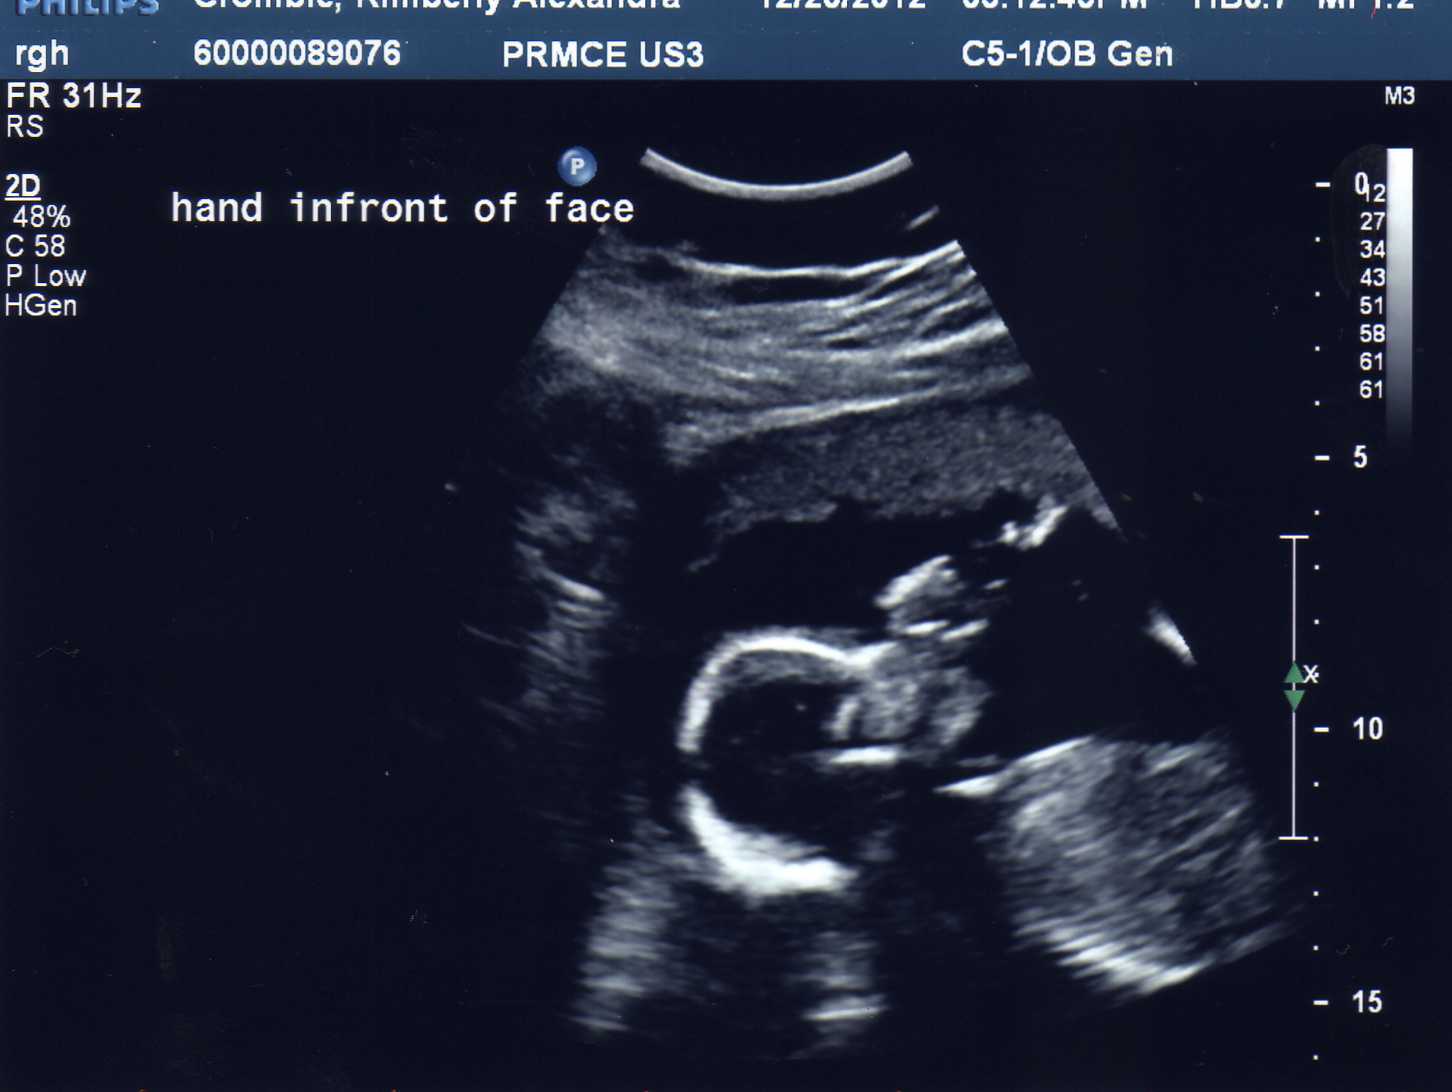

This is her with her hand in front of her face! I'm pretty sure she's actually rubbing her upper lip with her thumbs like I did (and may or may not still do when I'm tired, lol).